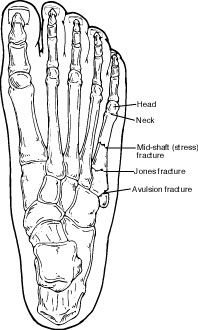

Fractures (breaks) are common in the fifth metatarsal – the long bone on the outside of the foot that connects to the little toe. Two types of fractures that often occur in the fifth metatarsal are:

Avulsion fracture. In an avulsion fracture, a small piece of bone is pulled off the main portion of the bone by a tendon or ligament. This type of fracture is the result of an injury in which the ankle rolls. Avulsion fractures are often overlooked when they occur with an ankle sprain.

Avulsion fracture. In an avulsion fracture, a small piece of bone is pulled off the main portion of the bone by a tendon or ligament. This type of fracture is the result of an injury in which the ankle rolls. Avulsion fractures are often overlooked when they occur with an ankle sprain. - Jones fracture. Jones fractures occur in a small area of the fifth metatarsal that receives less blood and is therefore more prone to difficulties in healing. A Jones fracture can be either a stress fracture (a tiny hairline break that occurs over time) or an acute (sudden) break. Jones fractures are caused by overuse, repetitive stress, or trauma. They are less common and more difficult to treat than avulsion fractures.

Other types of fractures can occur in the fifth metatarsal. Examples include mid-shaft fractures, which usually result from trauma or twisting, and fractures of the metatarsal head and neck.